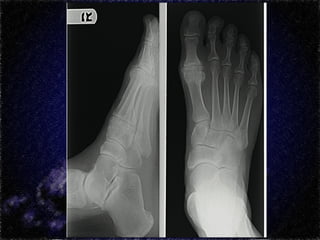

Radiologia

Estágios

Estágio I

Pequena diminuição do espaço articular

Osteófitos periarticulares

Convexidade da cabeça do 1° MTT diminuída

Sem alterações nos sesamóides

Estágio II

Espaço articular estreito

Achatamento da superfície articular

Lesões osteocondrais presentes

Elevatus do 1° raio

Estágio III

Perda do espaço articular

Osteófitos evidentes

Envolvimento imcompleto dos sesamóides

Corpos livres

Hipertrofia da articulação